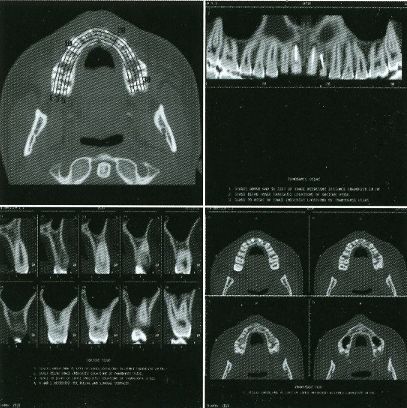

The first workstation to be seriously marketed was Voxelscope II (VS2) which had greatly enhanced volume memory and higher display resolution. Unfortunately, that came at a cost and it, and all its successors never even came close to achieving the true video-rate real-time performance of the VPP, which would have required the massively parallel technology in the Patent. But even very early on, VS2 had somewhat real software with a Graphical User Interface (GUI) and enough functions to be credible, at least for demos including instantaneous Multi-Planar Reformatting (MPR) which could display a slice though the object at any depth aligned with one of the principal axes (axial, saggital, or coronal) or at an arbitrary angle, as well as real-time (fraction of a second, but not video rate) 3-D shaded surface with density selection and slicing. A Motorola 68000-based VME bus single board computer replaced the PDP-11 or VAX (sorry DEC) and implemented the high level control and Graphical User Interface (GUI), ran the file system, and interfaced to the outside world.

These photos of the Voxelscope II screen are typical of the types of rendering provided by the system.

Voxelscope II Screen Shots. Combination of 3-D Shaded Surface, Multiplanar Reformatting, and Segmentation

Of course, once there was a real Marketing department, the real Software types (led by Eddie Wyatt) were always slowing things down anyhow in the interest of generality - or to concentrate on features users might actually care about! What a conecpt? ;-) One example was Multi-Planar Reformatting or MPR where a single cut along one of the principal planes - axial (XY), saggital (YZ), coronal (XZ) - or at an arbitrary angle or even curved cut through the object is displayed. MPR could have run at full video rates on any of the machines, but no matter how hard I tried to convince Software to improve the performance, it never chugged along at more than a couple frames per second. :( :) And large portion of the VS2 hardware capabilities were never exploited due to feature priority as determined by Marketing.